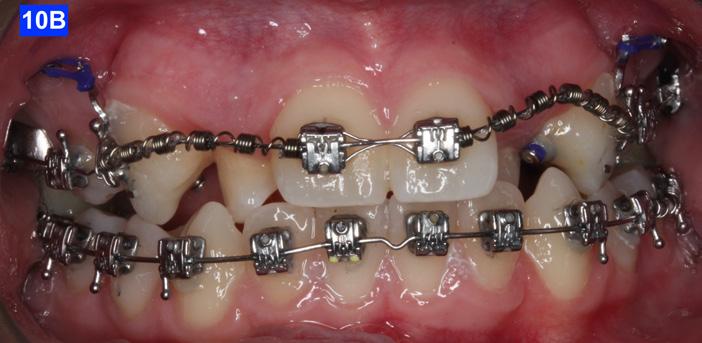

Clinical Micro-esthetic appraisal revealed Angle Class I molar relationship. The arches were narrow, there was crowding, and she had a posterior crossbite. The patient had 2.0 mm overjet and 1.5 mm overbite. There was an anterior cross bite on #12(7) and #22(10), which indicates Class III tendency. The lower airway was very narrow, only 5.0 mm; however, the patient denied SDB symptoms. She did, however, present with symptoms and signs of TMJ dysfunction (Figure 1-D, E, F, G, H,)

Figure 1D: Pre-treatment, frontal view

Figure 1E: Pre-treatment, right lateral view

Figure 1F: Pre-treatmrnt, left lateral view

Figure 1G: Pre-treatment, maxilla, occlusal view

Figure 1H: Pre-treatment, mandible, occlusal view